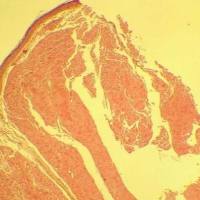

TUNEL凋亡显色法

TUNEL(TdT-mediated dUTP Nick-End Labeling)法检测细胞凋亡的原理是当细胞发生凋亡时,DNA内切酶被激活,核小 体间的基因组DNA被切断,暴露的3'-OH可以在末端脱氧核苷酸转移酶(Terminal Deoxynucleotidyl Transferase, TdT)加 上带有生物素(Biotin)标记的dUTP即Biotin-dUTP,随后于辣根过氧化物酶(HRP)标记的streptavidin结合,在HRP的催化 下通过DAB显色来显示凋亡细胞,从而可以通过普通光学显微镜检测到细胞凋亡。

- TUNEL法是一种分子生物学与形态学相结合的研究方法,可对完整的单个凋亡细胞或者凋亡小体进行原位染色,可以准 确反映细胞凋亡最典型的生物化学和形态特征。

- 可用于石蜡切片、冰冻切片、培养的细胞等进行细胞凋亡检测,灵敏度远比一般的组织化学和生物化学方法要高。